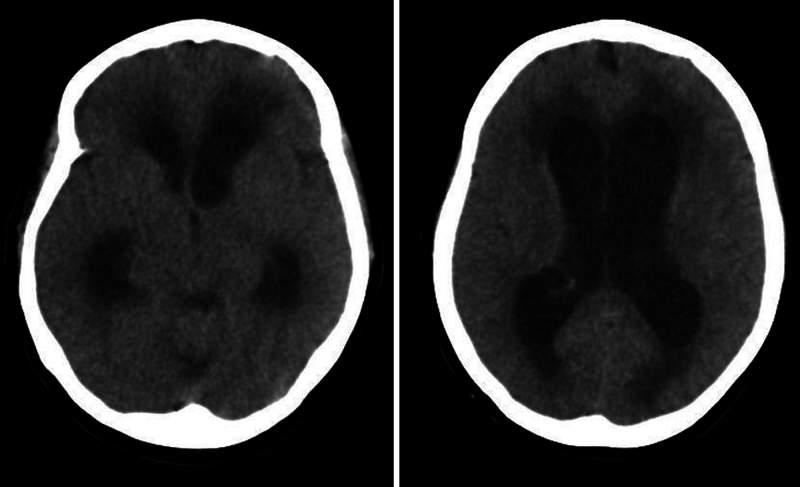

Observations: A 47-year-old female presented with a 3-month history of short-term memory disturbances, ultimately leading to loss of consciousness. Neuroimaging revealed symmetrical biventricular hydrocephalus accompanied by periventricular interstitial edema. A lumbar puncture indicated lymphocytic-dominant pleocytosis and reduced glucose levels. During the endoscopic approach, significant stenosis of the foramen of Monro was noticed and monroplasty and septostomy were performed. Pathological examination revealed granulomatous inflammation. At the 1-year follow-up, the patient demonstrated significant clinical and radiological improvement, with resolution of symptoms and hydrocephalus.

Abstract Image